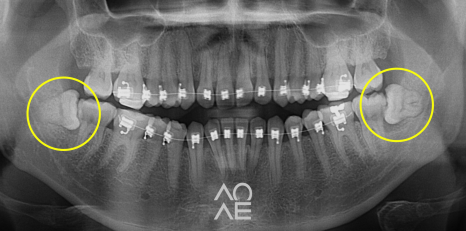

위 주소로 내원하신 학생분이신데요

저희 치과에서 교정을 하고 계셔서

사랑니의 존재는 익히 알고 있었는데요

파노라마라고 불리는 X-ray 를 보니

걱정하신 것 만큼 심각한 상황도 아니라서

당일 발치를 진행하였습니다

24.6.29

5분만에 발치하였습니다!

이번 발치 케이스도, 최소 침습과 최단 시간

발치로 깔끔하게 해결해드렸습니다!

| 발치 전 | 발치 후 |